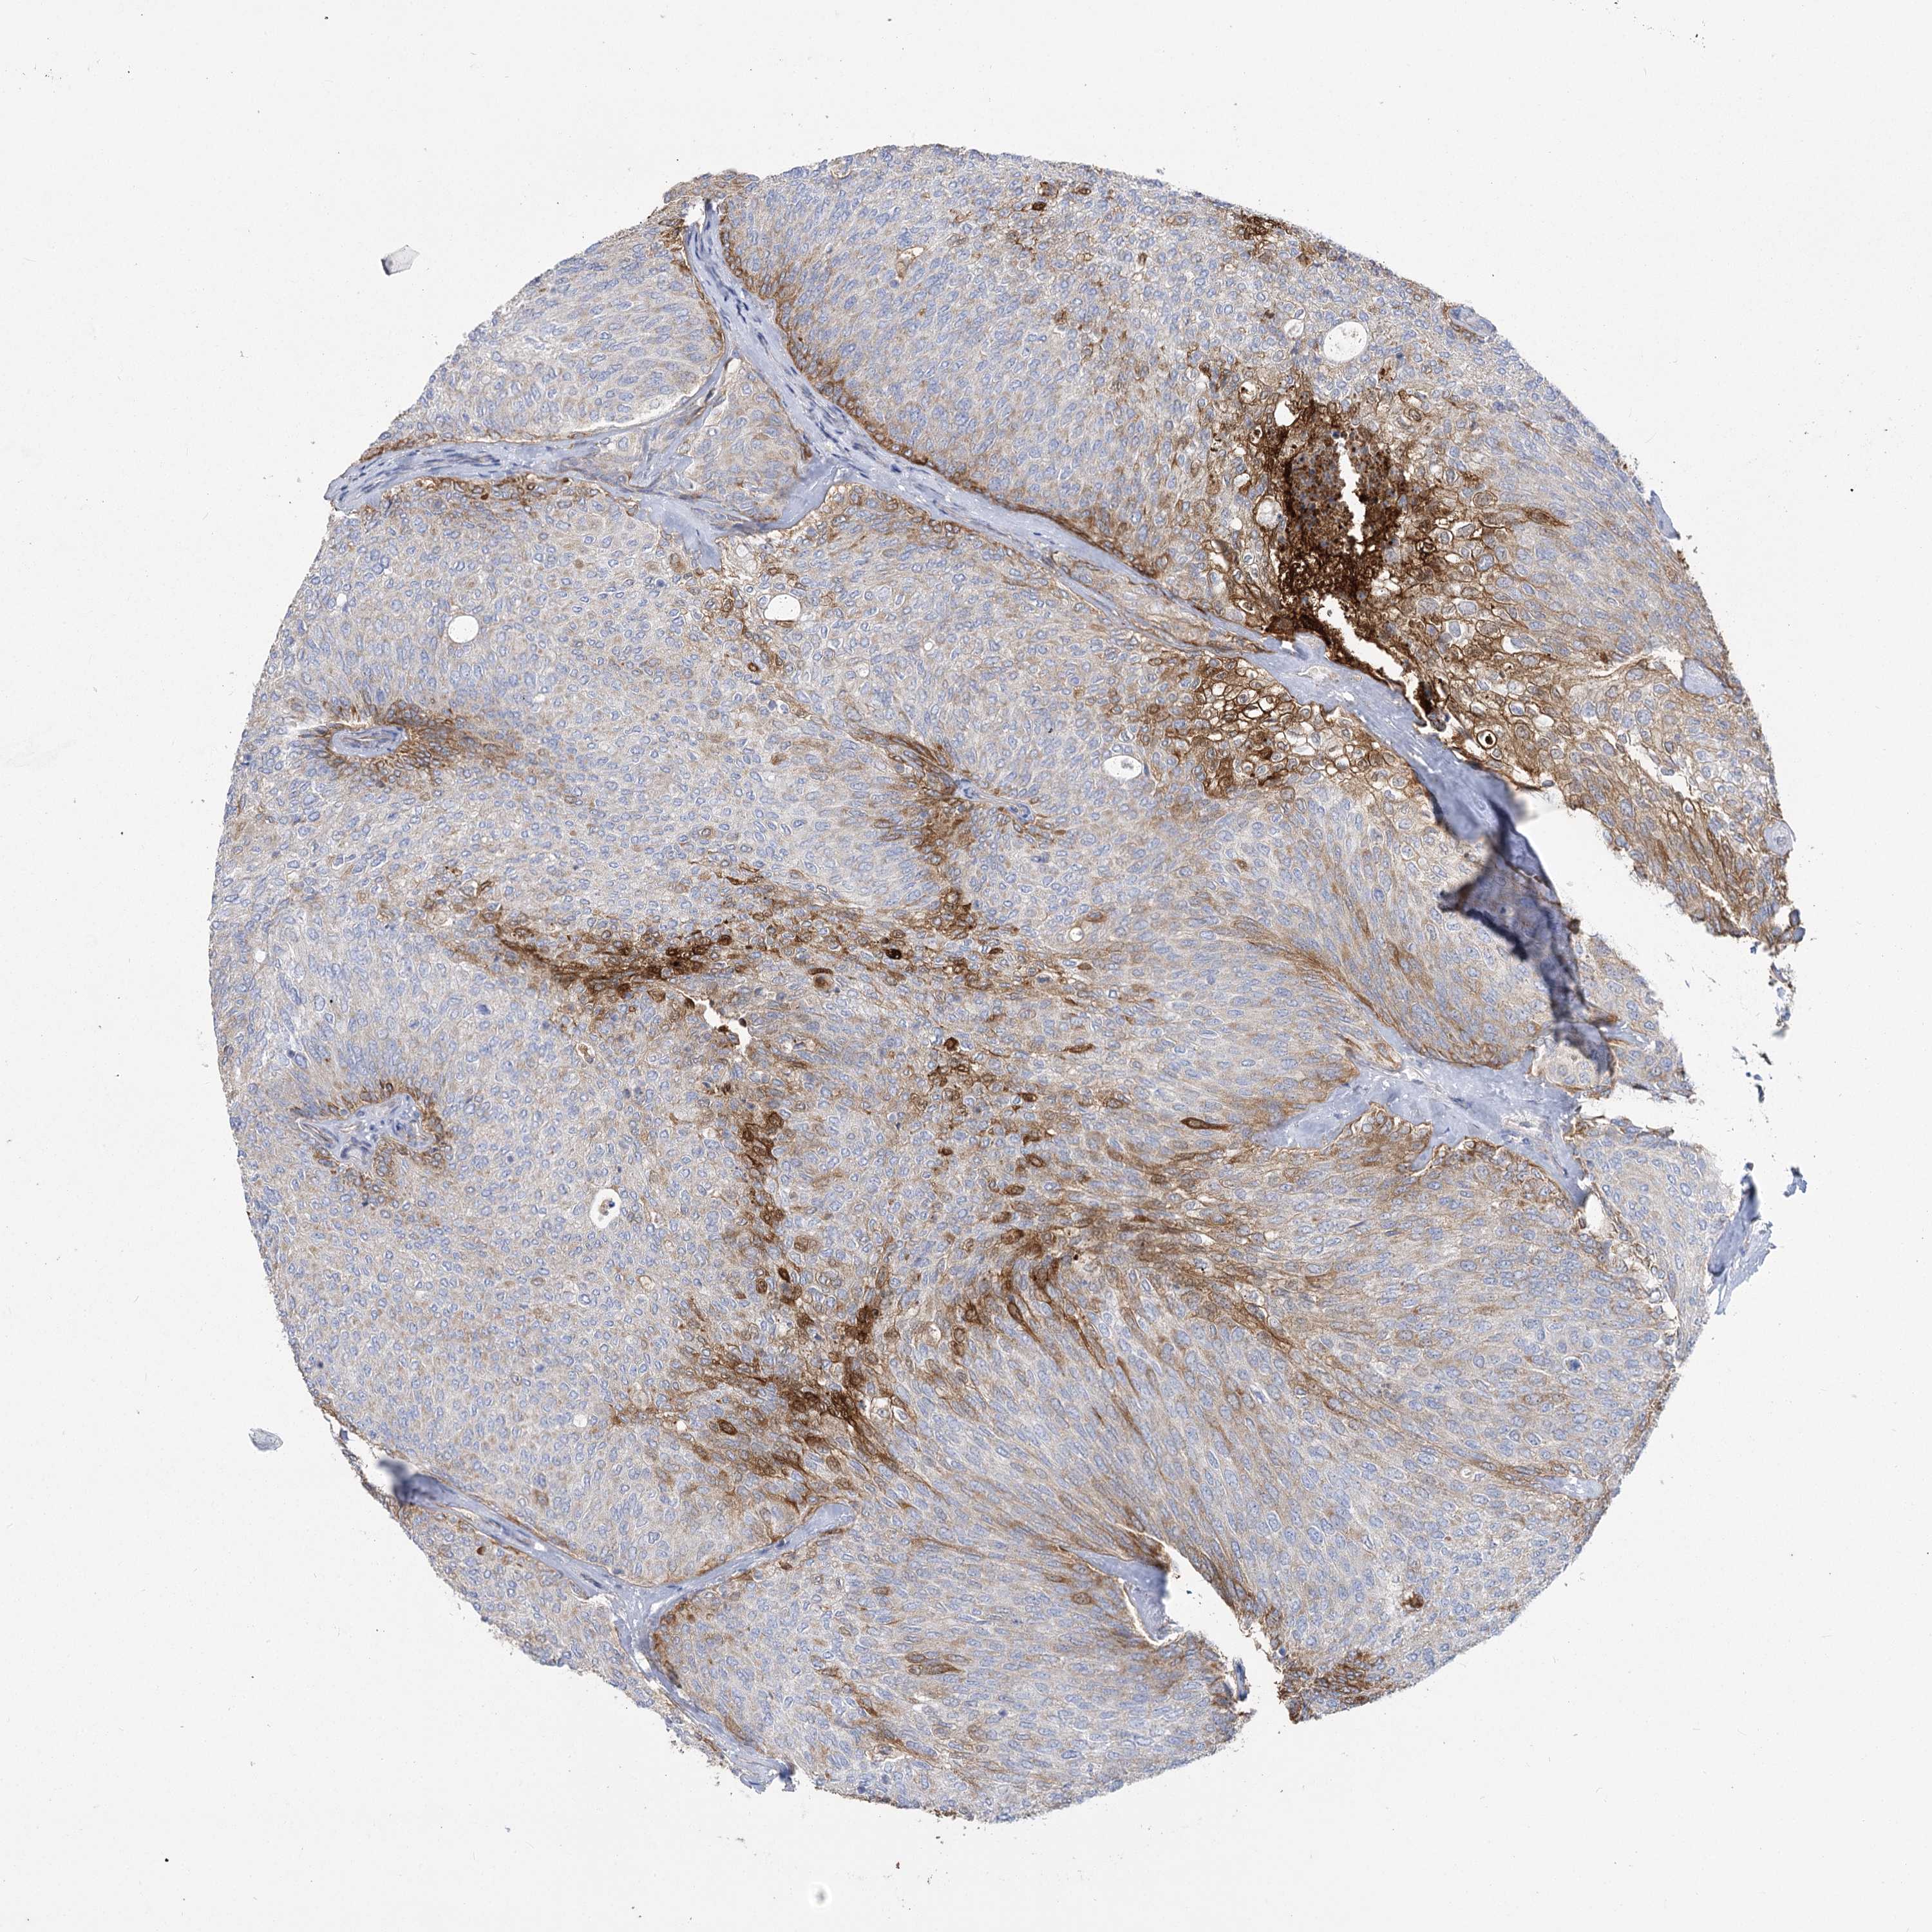

UROTHELIAL CANCER - Protein expressioni

A mouse-over function shows sample information and annotation data. Click on an image to view it in a full screen mode. Samples can be filtered based on level of antibody staining by selecting one or several of the following categories: high, medium, low and not detected. The assay and annotation is described here.

Antibody stainingi

Antibody staining in the annotated cell types in the current human tissue is reported as not detected, low, medium, or high, based on conventional immunohistochemistry profiling in selected tissues. This score is based on the combination of the staining intensity and fraction of stained cells.

Each image is clickable and will lead to virtual microscopy that enables deeper exploration of all samples and also displays staining intensity scores, fraction scores and subcellular localization as well as patient and tissue information for each sample.

Antibody HPA034705

Antibody HPA034706

Staining

High

Medium

Low

Not detected

Intensity

Strong

Moderate

Weak

Negative

Quantity

>75%

75%-25%

<25%

None

Location

Nuclear

Cytoplasmic/membranous

Cytoplasmic/membranous,nuclear

Urothelial carcinoma, High grade

Urothelial carcinoma, Low grade

Urothelial carcinoma, NOS